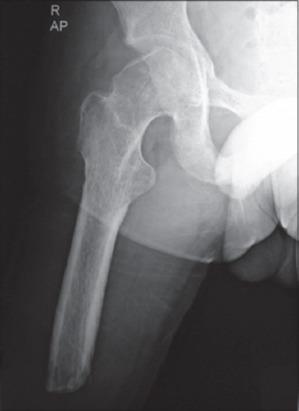

同侧创伤后膝上截肢患者的微创全髋关节置换术:一例报告

Minimally Invasive Total Hip Replacement in an Ipsilateral Post-traumatic above-knee Amputation: A Case Report.

We are presenting a case report of a 30-year-old male, who had previously underwent an above-knee amputation due to road-traffic accident, presenting 24 h after the injury with segmental fracture femur and popliteal artery laceration, for which the limb could not be salvaged. He had an impacted anteroinferior dislocation of the ipsilateral hip with significant cartilage damage of the femoral head which required open reduction. Subsequently, he developed traumatic arthritis of the involved hip which required conversion to an uncemented THR, using a minimally invasive (MIS) anterolateral approach. The preoperative management, surgical technique, and postoperative rehabilitation are described to highlight the technical challenges, these lower limb amputees may present along with review of literature of such rare cases.

我们报告一例30岁男性患者,该患者此前因道路交通事故接受了膝上截肢手术,受伤24小时后出现股骨干骨折和腘动脉撕裂伤,肢体无法挽救。他同侧髋关节存在嵌顿性前下脱位,股骨头软骨严重受损,需要切开复位。随后,他出现了受累髋关节的创伤性关节炎,需要采用微创(MIS)前外侧入路转换为非骨水泥型全髋关节置换术。描述了术前管理、手术技术和术后康复情况,以突出这些下肢截肢患者可能面临的技术挑战,并回顾此类罕见病例的文献。